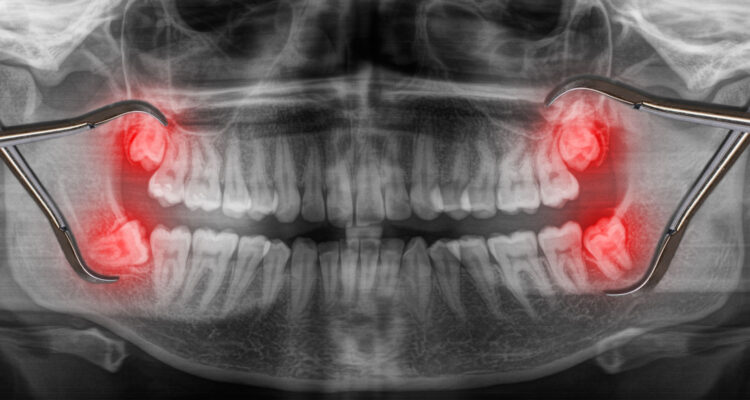

Что такое ретинированные зубы мудрости?

Ретинированный зуб мудрости – это зуб, коронка которого по тем или иным причинам не прорезалась полностью. Ретенция бывает полной — когда коронка полностью находится в альвеолярной кости или неполной — когда коронка частично или полностью находится под слизистой десен.

Полная ретенция

Неполная ретенция